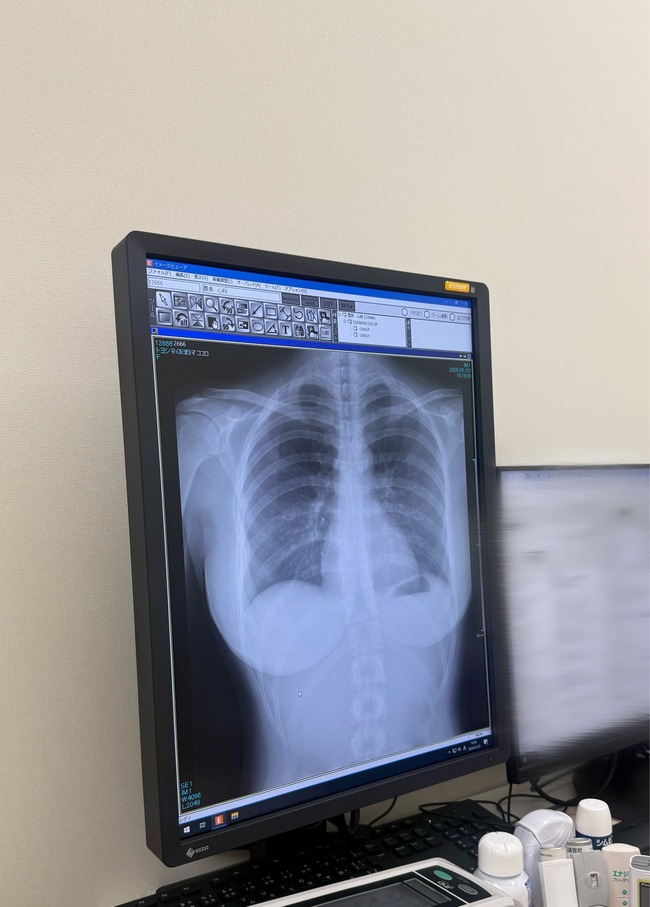

レントゲンがヤバいと話題に

肺綺麗でした pic.twitter.com/oprlolFN39

— 豊島 心桜 (@CocoroToyoshima) January 23, 2026

本当に綺麗な肺だ

推しのレントゲン公開

これ、自分のレントゲンと比べてマジで心臓とか肺が整ってて羨ましい